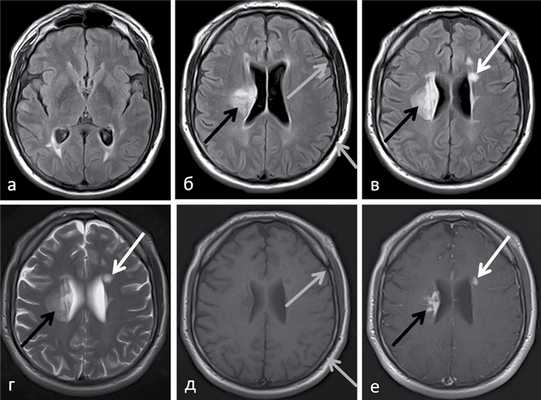

(а) МРТ, Т2-ВИ FSE, аксиальный срез: у младенца с гипотонией и энцефалопатией определяется повышение интенсивности сигнала от головок хвостатых ядер и скорлупы. Обратите внимание на вовлечение наиболее задних отделов скорлупы. Центральные отделы скорлупы характеризуются гиперинтенсивным сигналом.

(б) МРТ, карта ИКД, аксиальный срез: у того же пациента определяется ограничение диффузии в области головок хвостатых ядер и большей части пораженной скорлупы билатерально, тогда как центральные отделы скорлупы характеризуются повышенным коэффициентом диффузии что указывает на предшествующее кавитирующее поражение.

(а) МРТ, Т2-ВИ, аксиальный срез: отмечается повышение интенсивности сигнала от ножек мозга, красных ядер и покрышки среднего мозга (включая периакведуктальное серое вещество). Эти структуры являются частой локализацией поражения ствола мозга при синдроме Лея.

(б) МРТ, ДВИ, аксиальный срез: определяется ограничение диффузии (гиперинтенсивные участки) в пораженных участках среднего мозга. Ограничение диффузии указывает на острую стадию поражения, в то время как повышение диффузии больше указывает на хроническую стадию поражения.

(а) МРТ, Т2-ВИ, аксиальный срез: определяется повышение интенсивности сигнала от колена и валика мозолистого тела, распространяющееся на пери вентрикулярное и глубокое белое вещество, а также задние бедра внутренних капсул.

(б) Одновоксельная протонная МР-спектроскопия (ТЕ = 144 мс): у того же пациента определяется минимальный пик лактата на 1,33 ppm и аномальный пик на 2,4 ppm, что соответствует сукцинату. Был поставлен диагноз "дефицит сукцинатдегидрогеназы вследствие БСНА-мутации".